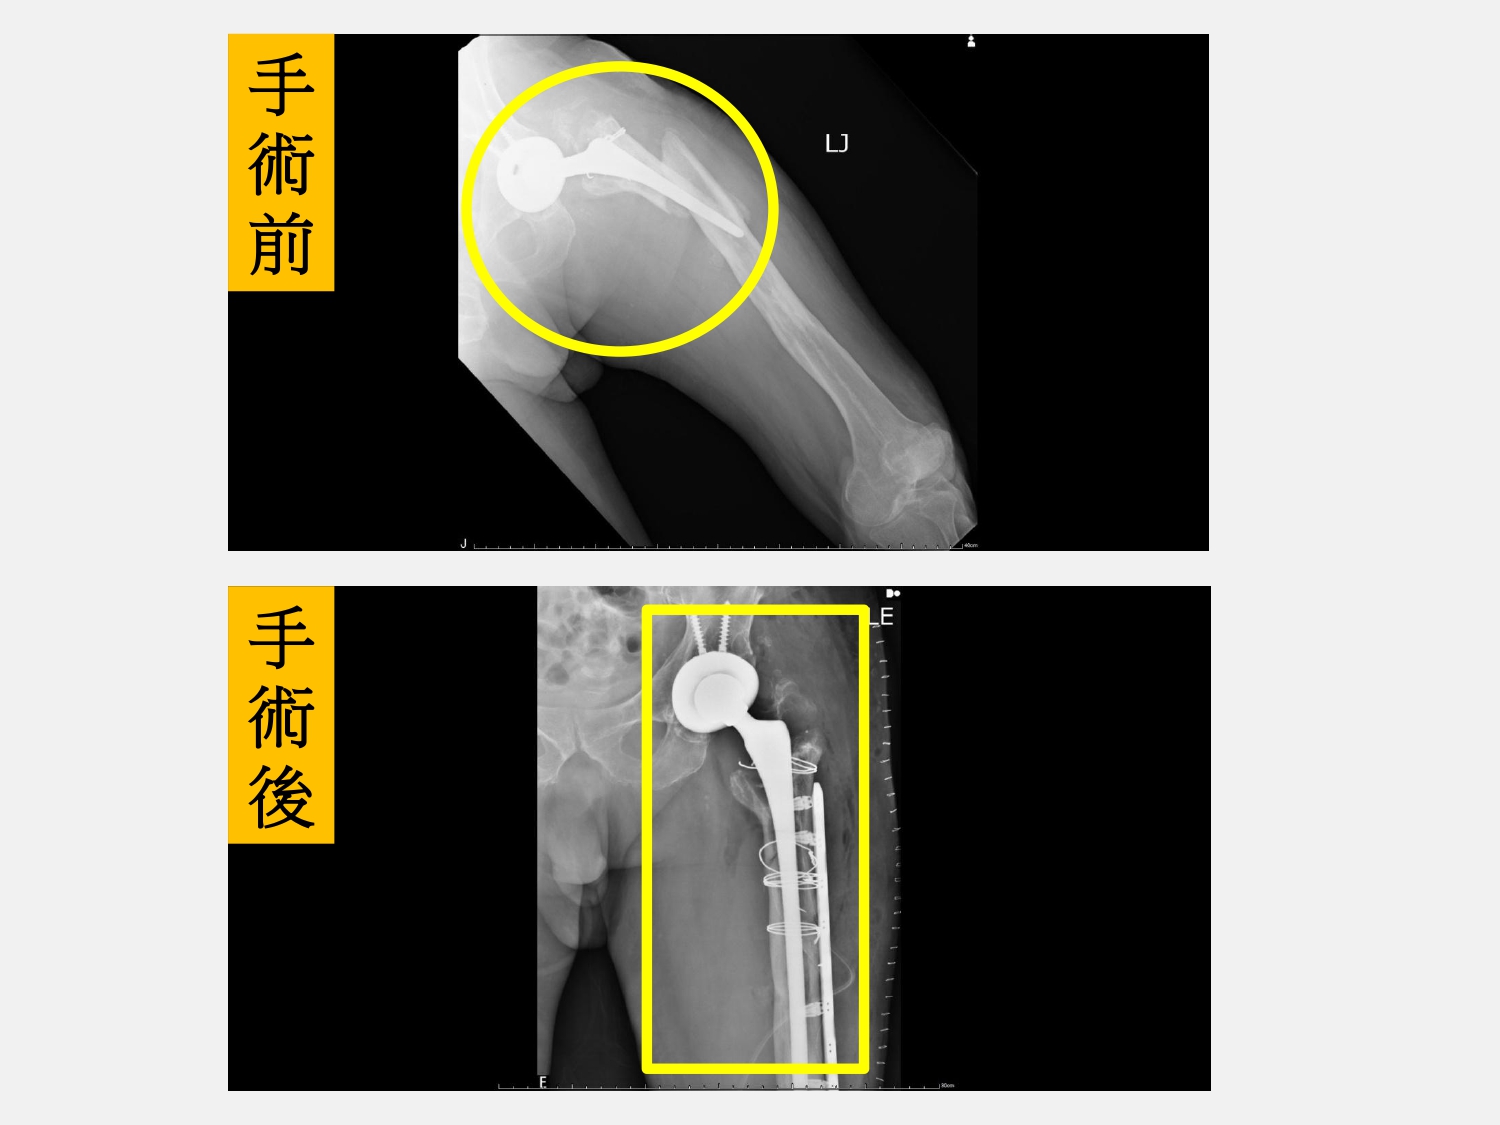

圖:(上)人工髖關節旁的股骨粉碎性骨折,原本的人工關節也整個鬆動(圓圈處)。(下):手術重新置換人工關節並固定骨折(方框處)/大里仁愛醫院提供

台中市大里區一名82歲劉姓男子有高血糖、高血壓和高血脂等病史,兩側髖關節曾經接受過人工關節置換手術。今年中秋節連假與家人賞月烤肉同樂時不小心滑了一跤後跌坐在地上,左腳痛到無法動彈,家人趕緊將劉先生送到大里仁愛醫院急診室,經檢查後才發現是人工髖關節旁的股骨粉碎性骨折,而且原本的人工關節也整個鬆動了。經骨科部黃贊文部長啟動「宜樂適快速康復手術療程(ERAS)」後,安排骨質疏鬆藥物治療,並配合健保署的「手術後疼痛中醫輔助療法」,在中西醫合併治療下,劉先生已順利出院。只是一個單純的滑倒卻造成如此嚴重的後果,劉先生現在回想起來,仍是心有餘悸。

黃贊文部長說明,劉先生因為長期忽視骨質疏鬆症,僅是滑了一跤就造成粉碎性骨折且人工關節也鬆動失去功能。此次手術不僅要重新置換人工關節還要固定骨折,由於劉先生年事已高,跨團隊整合治療才能給高齡長者帶來安全又好的治療效果。